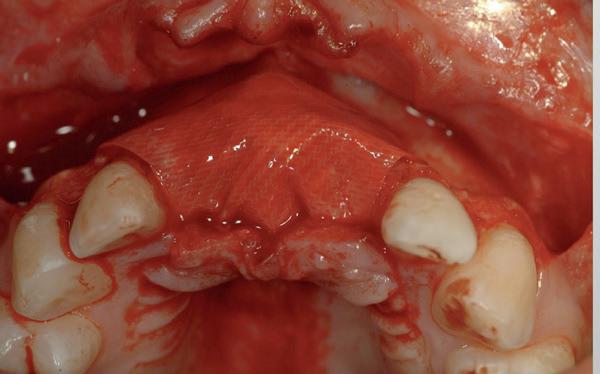

In het onderfront werd autoloog bot geoogst uit de kin regio ten behoeve van augmentatie (afbeelding

9. Botopbouw onderfront

9). In de bovenkaak werd bilateraal een sinuslift uitgevoerd. Aansluitend werden in beide kaakhelften implantaten geplaatst (afbeelding 10).